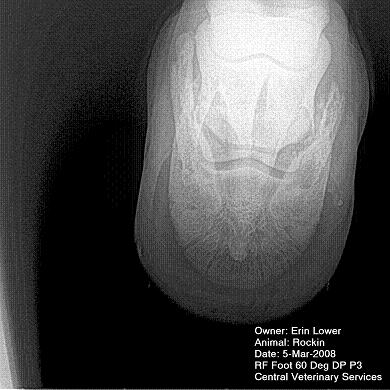

So, Rockin's x-rays were sent to a radiologist and he confirmed "normal" changes in the navicular bones for a horse her age, but slightly more significant ones in the right (sore) foot.

She also has sidebone in both fronts, but apparently that isn't causing any discomfort.

Finally, she has a "small chronic exostosis on the lateral aspect of the proximal phalanx" which, according to the radiologist, shouldn't be causing discomfort but I have read that these can be mild-to-moderately painful... I wouldn't mind another opinion on that.

I will attach as many images as possible from her x-rays (there are many different views). I don't have any pics of the feet as someone deleted them from my camera before I could download them. I'll try to take pics next time she is trimmed. Please, anyone with knowledge of hooves, give any opinions that you might have (especially Dr. O!)

I cannot rule out lesions based on these images but I will take your radiologist's word that he does not see significant lesions. The exostosis on the RF would be above the level of a well conducted PDN which I believed blocked the lameness before?

DrO